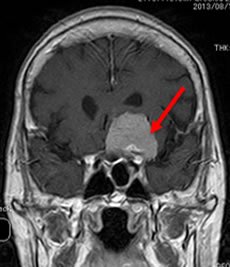

当院での症例をお示しします。症例は66才女性、進行する左眼の視力(左:手動弁)、視野障害にて当院来院。MRIにて赤矢印のように左蝶形骨内側に大きな腫瘍を認めます。開頭手術治療前に腫瘍の栄養血管にカテーテルを入れて、固体塞栓物質を造影剤と混ぜて注入します。最後に再開通しない様プラチナコイルを留置して終了します。その2日後に腫瘍摘出を行いましたが、出血は少量で輸血も行っておりません。視力も左は1.5まで改善し、患者さんは元気で退院しました。(図1-a・b、図2-a・b、図3-a・b、図4-a・b)

図3-a:術前 |

図3-b:術後 |